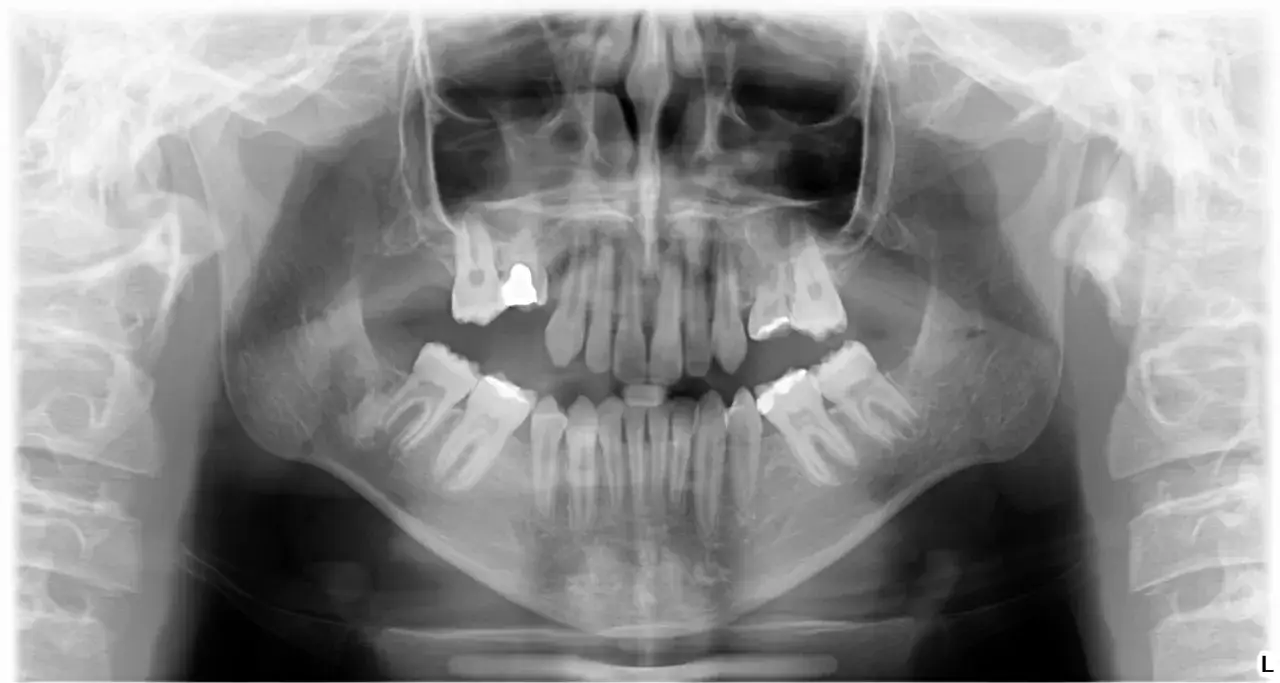

Tak, zęby trzonowe wypadają u dzieci, ale kluczowe jest rozróżnienie, o które zęby trzonowe chodzi. Tylko mleczne zęby trzonowe wypadają naturalnie, ustępując miejsca zębom stałym. Co ważne, ich miejsce zajmują zęby przedtrzonowe, a nie kolejne trzonowce. To bardzo istotna różnica, którą często pomijamy.

Natomiast stałe zęby trzonowe, czyli popularne "szóstki", "siódemki", a w późniejszym wieku "ósemki" (zęby mądrości), nie mają swoich mlecznych odpowiedników. Oznacza to, że wyrzynają się one za ostatnimi zębami mlecznymi i powinny pozostać w jamie ustnej dziecka na całe życie. Ich wypadnięcie jest zawsze sygnałem alarmowym i wymaga natychmiastowej konsultacji ze stomatologiem.

Stałe trzonowce, czyli szóstki, siódemki i ósemki

Stałe zęby trzonowe to zupełnie inna kategoria. Wyrzynają się one za ostatnimi zębami mlecznymi i nie zastępują żadnych zębów mlecznych. Pierwsze stałe trzonowce, powszechnie nazywane "szóstkami", pojawiają się w jamie ustnej dziecka około 6. roku życia, często niezauważone przez rodziców, ponieważ nie poprzedza ich wypadnięcie mleczaka. Są to zęby, które powinny służyć dziecku przez całe życie. Ich wypadnięcie, ruchomość lub jakikolwiek uraz, który je dotyka, jest zawsze sygnałem alarmowym i wymaga pilnej interwencji stomatologicznej. Nie ma tu mowy o naturalnej wymianie – stałe trzonowce są zębami docelowymi.

| Pierwsze stałe trzonowce (szóstki) | Nie dotyczy | Około 6. roku życia |

| Mleczne zęby trzonowe | Między 10. a 12. rokiem życia | Zastępowane przez zęby przedtrzonowe około 13. roku życia |

| Stałe trzonowce (siódemki, ósemki) | Nie dotyczy | Później niż szóstki, ósemki mogą pojawić się nawet po 18. roku życia |